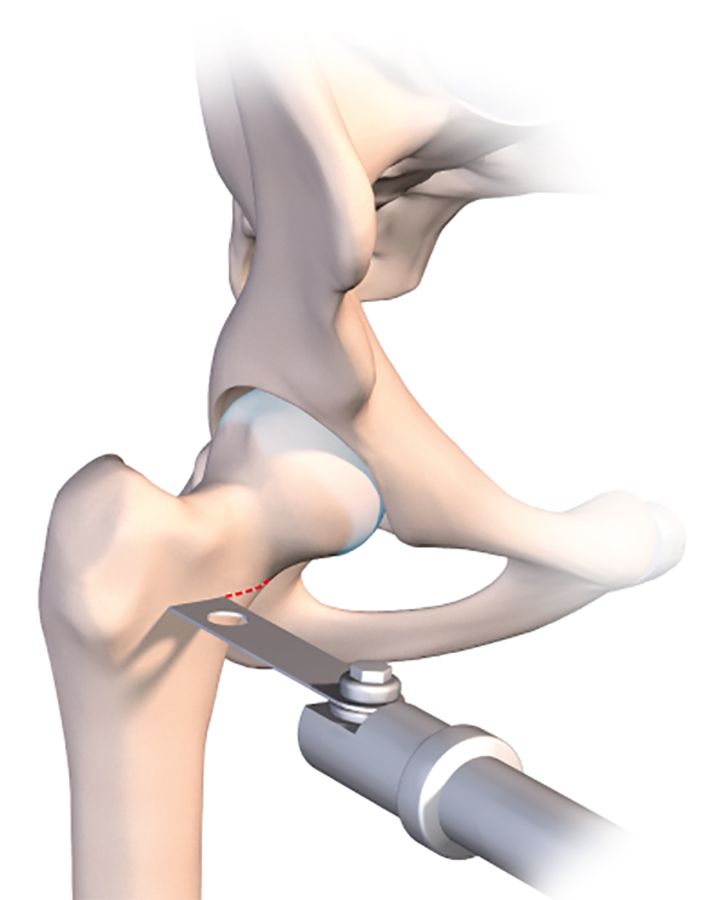

Just before using the orthopaedic table to begin the compression, it is a good idea to use a tibial drill guide (as for cruciate ligament repair) (Figs. 2b, c, d).

This makes it much easier to guide a pin into the osteotomy line that has just been created. The pin should of course sit just within the osteotomy line, without going any further. Applying compression will close the line and fix the pin in the neck and head of femur. With the osteotomy line closed and the pin in place, the final stage is to insert a 7mm cannulated screw to stabilize the fixation. A second or even third screw may be used if necessary. The image intensifier should be used to check the correct placement of the screws (Fig. 2e).